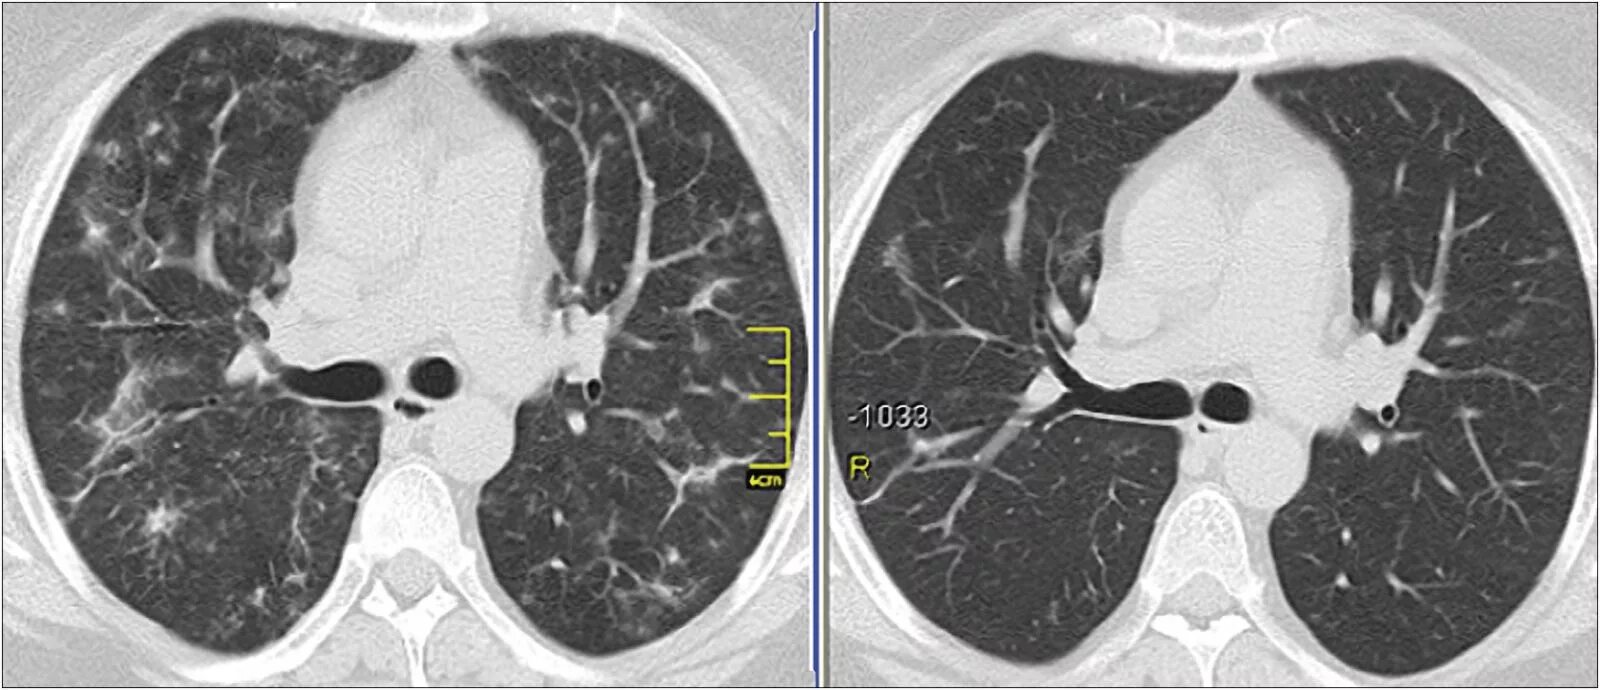

Болит кт